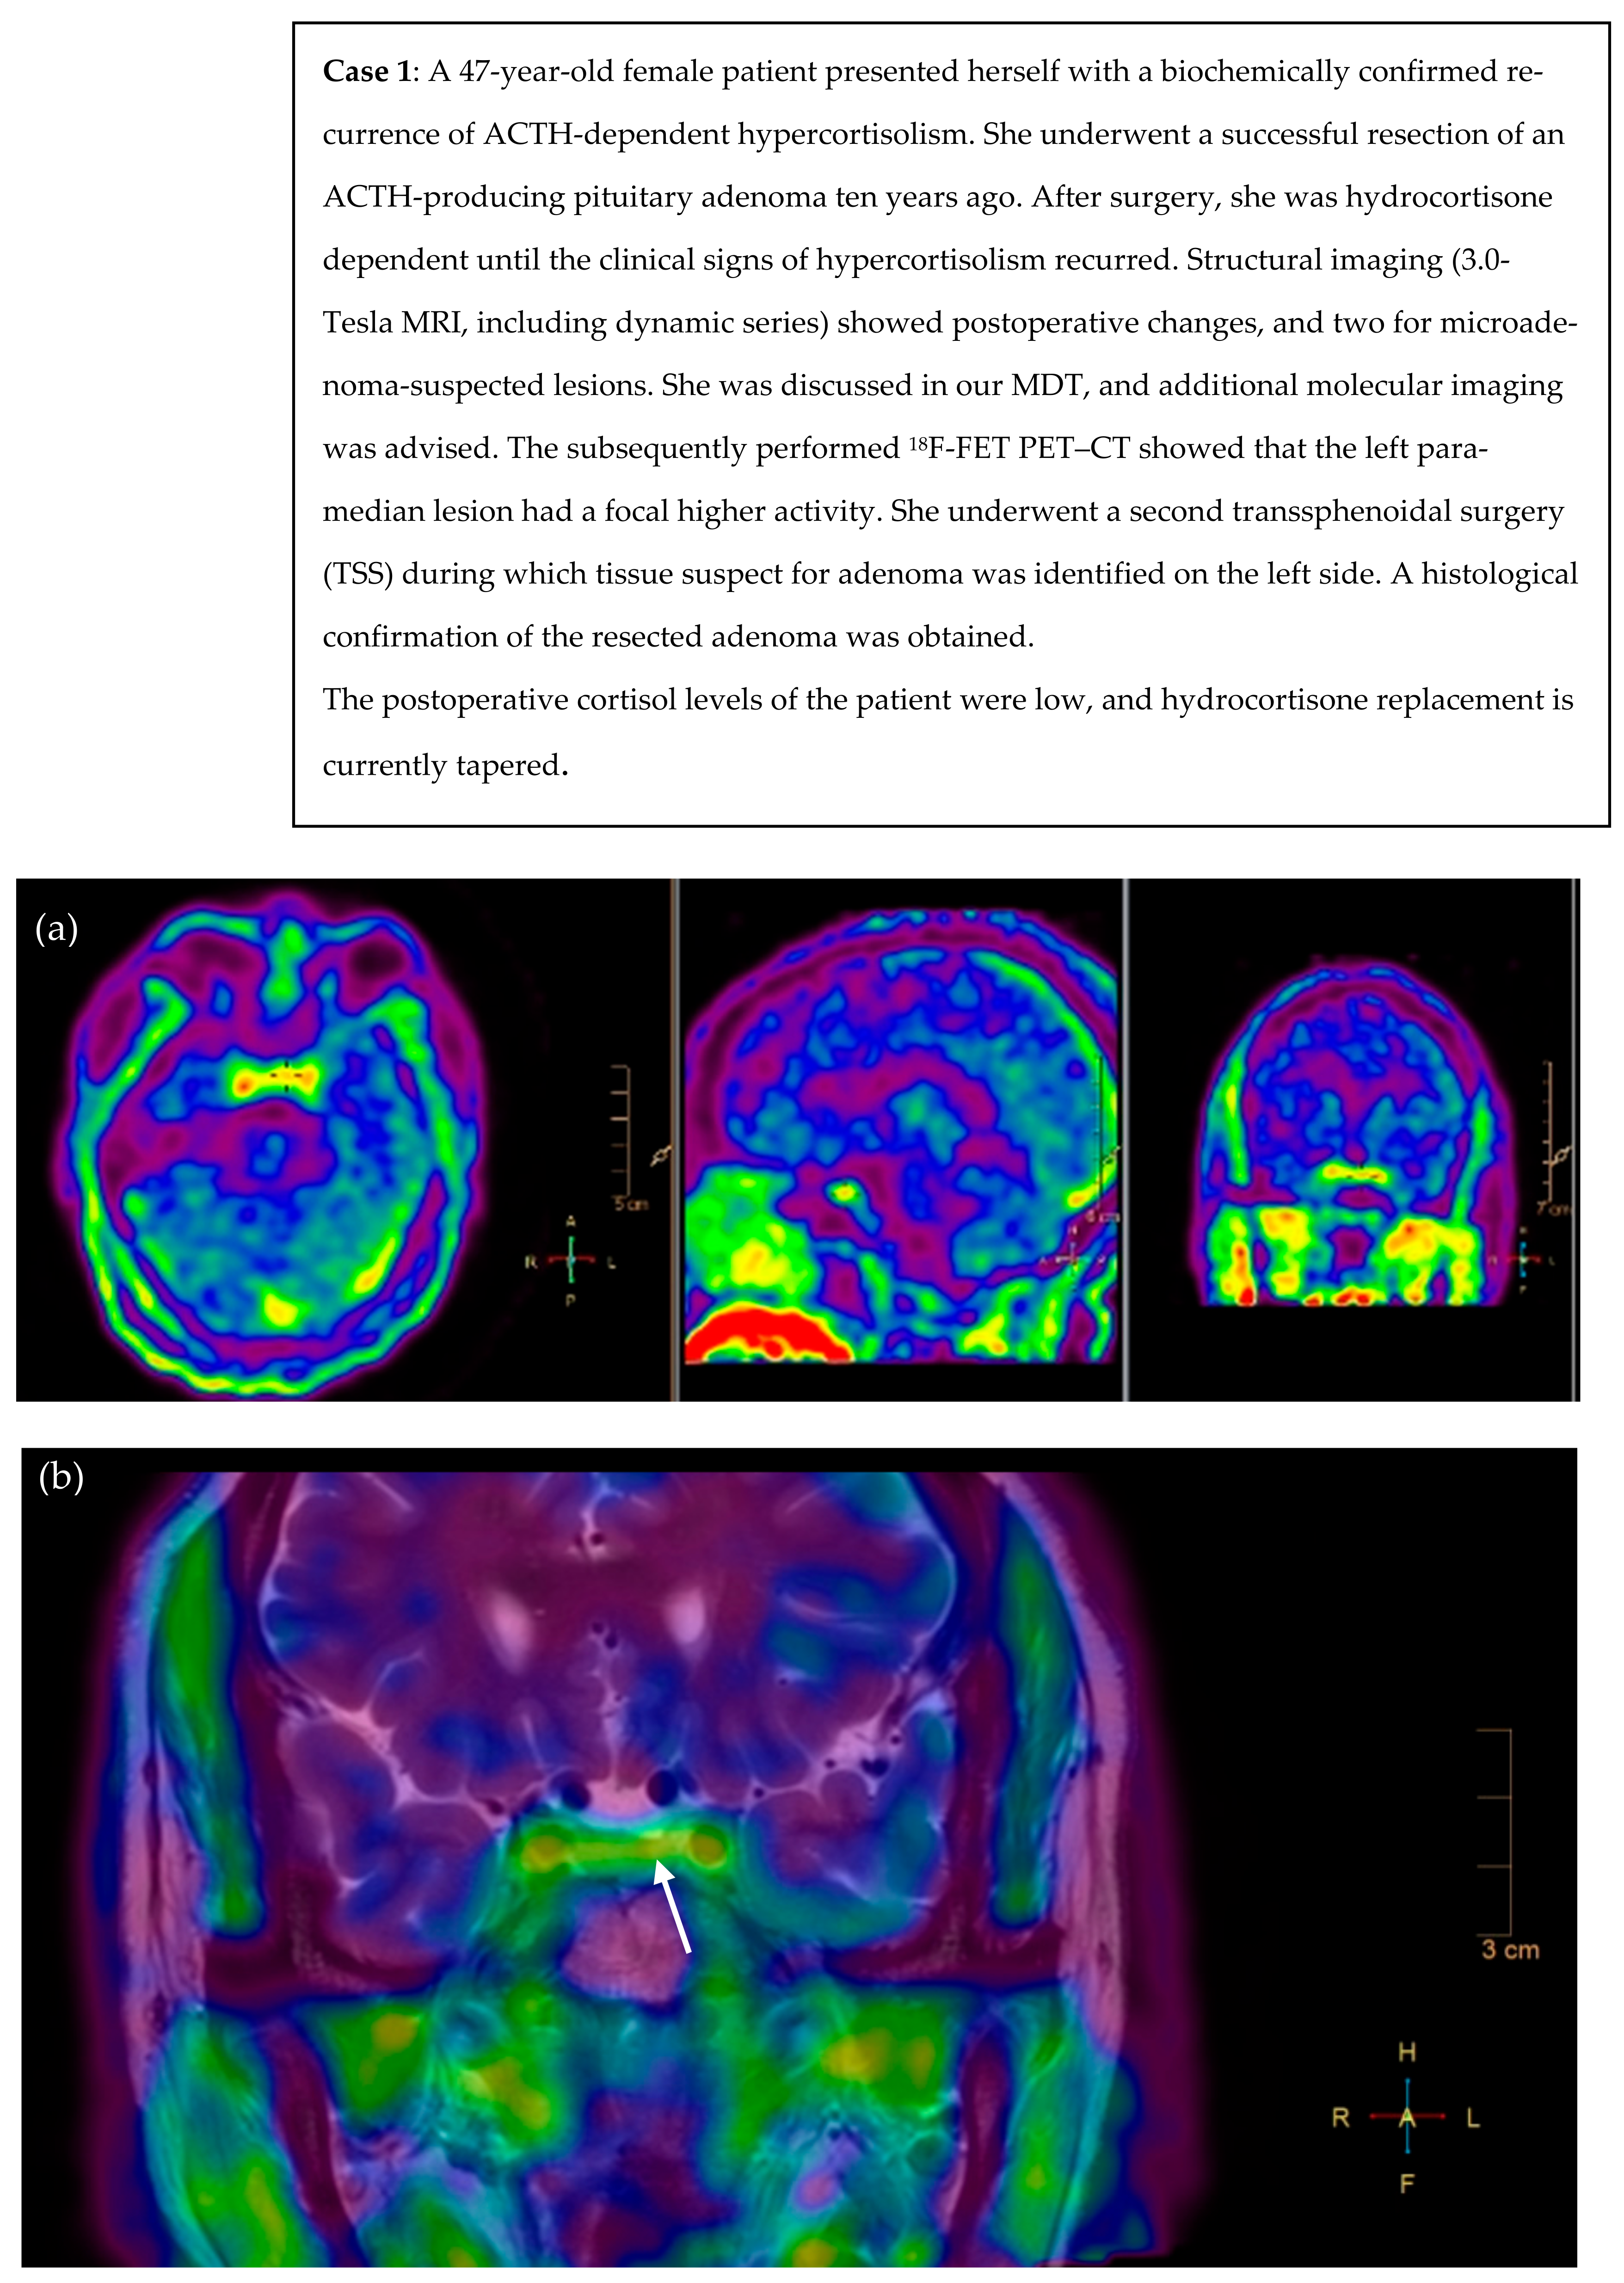

3.2. Illustrative Cases

- Persistent or selected cases of recurrent Cushing’s disease (equivocal biochemical response) after TSS and with histological confirmation, but no or inconclusive adenoma remnant localization on the pituitary MRI (illustrative cases 1 and 2).